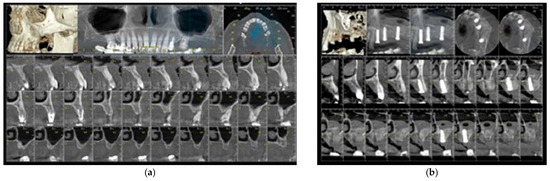

This Special Issue, “Innovations and Challenges in Dental Implantology”, seeks to highlight cutting-edge research and practical insights into key aspects of implantology. Topics of interest include advancements in osseointegration, biomaterials, autologous blood-derived products, and enhanced approaches to guided bone regeneration and bone augmentation. Contributions addressing sinus elevation techniques, peri-implantitis prevention and treatment, soft tissue management, and strategies to mitigate implant failures are highly encouraged. Furthermore, we welcome studies focusing on surgical or non-surgical salvage techniques, providing valuable insights into the management of complications in dental implantology.